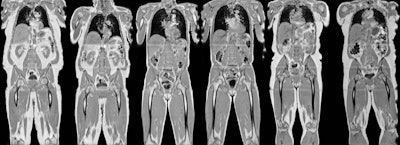

A team of researchers from the U.K. led by Brandon Whitcher, PhD, of the University of Westminster in London studied over 3,000 patients in the UK Biobank who received knee-to-neck MRI scans at their first imaging visit and then again two years later. They found significant changes in visceral adipose tissue, intermuscular fat, and grip strength, even in participants without increased body mass index and waist size.

In 3,088 cases from the UK Biobank, deep-learning algorithms were used to segment and perform volumetric assessment of the liver, pancreas, spleen, and kidneys on MRI. The researchers also evaluated for changes in adipose tissue, skeletal muscle, and the vascular system. What's more, they measured the levels of proton density fat fraction and iron concentration for each participant.

Using an automated image processing pipeline, 27 image-derived phenotypes were generated from the abdominal MR protocol and then combined with physiological measures related to the disease or physiological condition. After identifying combinations of image-derived phenotypes and disease, the researchers found that the trajectory of longitudinal changes in body composition image-derived phenotypes was dependent on the study participants' physiological state.